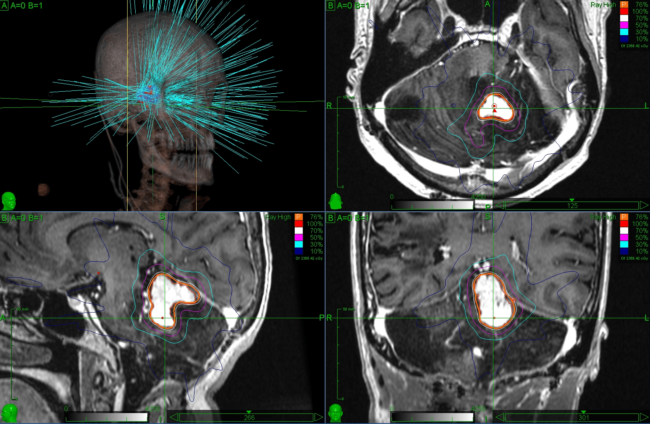

Análisis del conectoma del núcleo accumbens: refinando la diana de la radiocirugía para los trastornos adictivos. Jose E. Chang. William O. Contreras Lopez. Richard Gonzalo Párraga .Jorge Torres Monterrosa. Larissa Merlos Salazar. Eduardo E. Lovo Resumen Esta investigación estudia las conexiones del núcleo accumbens (NAc) para mejorar la precisión de la rad/cirugía estereotáxica (radiosurgery) como…